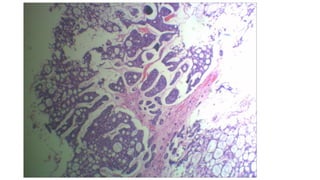

Section studied from R nasal mass shows tumor composed of tumor

cells arranged predominantly in cribriform and tubular pattern

tumor cells are small, round to oval with scanty cytoplasm,

hyperchromatic nuclei and indistinct cell border

pseudocyst formed by the tumor cells are filled with eosinophilic

hyaline material.

tumor cells are seen infiltrating the adjacent mucosal glands and

interstitium.

Neural invasion is seen

adjacent attached respiratory epithelium show normal histology

• Microscopic examination: Sectionstudied from R nasal mass shows tumor composed of tumor cells arranged predominantly in cribriform and tubular pattern tumor cells are small, round to oval with scanty cytoplasm, hyperchromatic nuclei and indistinct cell border pseudocyst formed by the tumor cells are filled with eosinophilic hyaline material. tumor cells are seen infiltrating the adjacent mucosal glands and interstitium. Neural invasion is seen adjacent attached respiratory epithelium show normal histology

• Impression: Adenoid cysticcarcinoma with perineural invasion